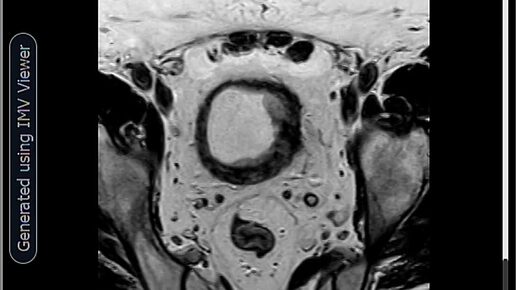

МРТ- Менингоцеле⁠⁠

Менингоцеле — это один из видов Spina bifida (порока развития, известного как «расщепление позвоночника»). Это врожденный дефект, при котором позвоночный канал и позвоночник не закрываются полностью во время внутриутробного развития плода. При менингоцеле через костный дефект в позвоночнике выпячиваются мозговые оболочки — защитные мембраны, окружающие спинной мозг. Эти оболочки образуют заполненный спинномозговой жидкостью мешок (грыжу). Ключевой момент: сам спинной мозг и нервные корешки обычно не вовлечены в этот мешок или расположены правильно...